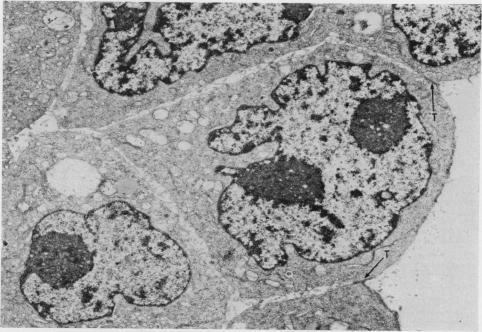

To analyse the effect of ethylenediamine tetraacetate (EDTA) on tumour cell adhesiveness, fine structure of intercellular junctions of rat ascites hepatoma cells AH136B and AH7974 (both forming cell islands in vivo) was first compared. The close contact of the apical portion of both cell islands was composed of tight junctions with a narrow gap. The close contact of the inner portion of AH136B cell islands was largely by simple apposition, while that of AH7974 cell islands had many intermediate junctions and desmosomes. Treatment with EDTA (2 mM) induced morphological alteration of simple apposition, intermediate junctions and desmosomes, but tight junctions remained intact. The effect of EDTA on such junctional complexes seemed to be partially reversible on readministration of Ca ions. Changes in desmosomes, as confirmed on AH7974 cells, were initiated by disappearance of the central disc of electron-dense materials, followed by marked opening of intercellular space and disappearance of endoplasmic laminar plaque. These results suggest that Ca ions may be concerned with maintaining the integrity of junctional complexes other than tight junctions.

为分析乙二胺四乙酸(EDTA)对肿瘤细胞黏附性的影响,首先比较了大鼠腹水肝癌细胞AH136B和AH7974(两者在体内均形成细胞岛)细胞间连接的精细结构。两个细胞岛顶端部分的紧密接触由间隙狭窄的紧密连接组成。AH136B细胞岛内部分的紧密接触主要是简单并置,而AH7974细胞岛的紧密接触有许多中间连接和桥粒。用EDTA(2 mM)处理可诱导简单并置、中间连接和桥粒的形态改变,但紧密连接保持完整。再次给予钙离子后,EDTA对这种连接复合体的作用似乎部分可逆。在AH7974细胞上证实,桥粒的变化始于电子致密物质中央盘的消失,随后细胞间隙明显增宽,内质层板消失。这些结果表明,钙离子可能与维持除紧密连接之外的连接复合体的完整性有关。